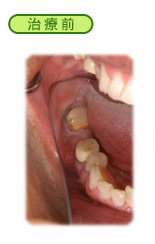

歯周病

歯周病とは、歯の周囲に付着したプラーク(歯垢)が歯と歯肉の隙間に入り込み、歯を支えている骨を溶かしてしまう病気です。

歯肉が腫れる、歯肉から出血する、口臭が気になる、歯がグラグラするなどの症状があれば、歯周病にかかっているのかもしれません。

以前は「不治の病」とさえ言われていた歯周病も、現在では進行を阻止することが可能となり、状況によっては元の健康な状態に戻すこと(再生療法)さえ出来るようになってきました。